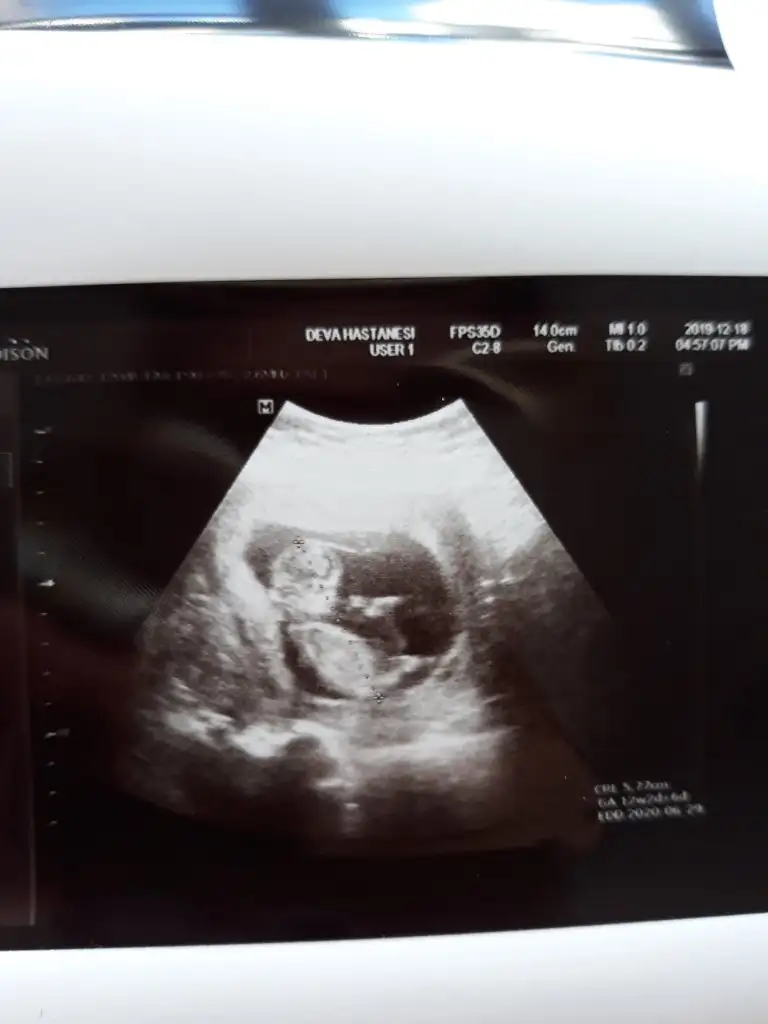

Bunada bakarmisiniz 12 +2 haftalık cok merak ediyorum🙏😊

Eklentiler

• 20191218_102250.webp

20191218_102250.webp

16,6 KB · Görüntüleme: 71

• 20191218_102242.webp

20191218_102242.webp

29,1 KB · Görüntüleme: 53

Ikra meyra Ikra meyra 12+0 ultrasonu:)

363C7916-792F-4CE1-9F27-A686FE4C5637.jpeg

Doktor %80 erkek dedi sizce net midir? Cok arkdsm

Bu haftalara guvenme her gittigimde farkli sey soyluyor doktor dedi nuba gorede erkek gibi ama merak ediyorm onceden boyle olup sonra kiz cikan var mi?